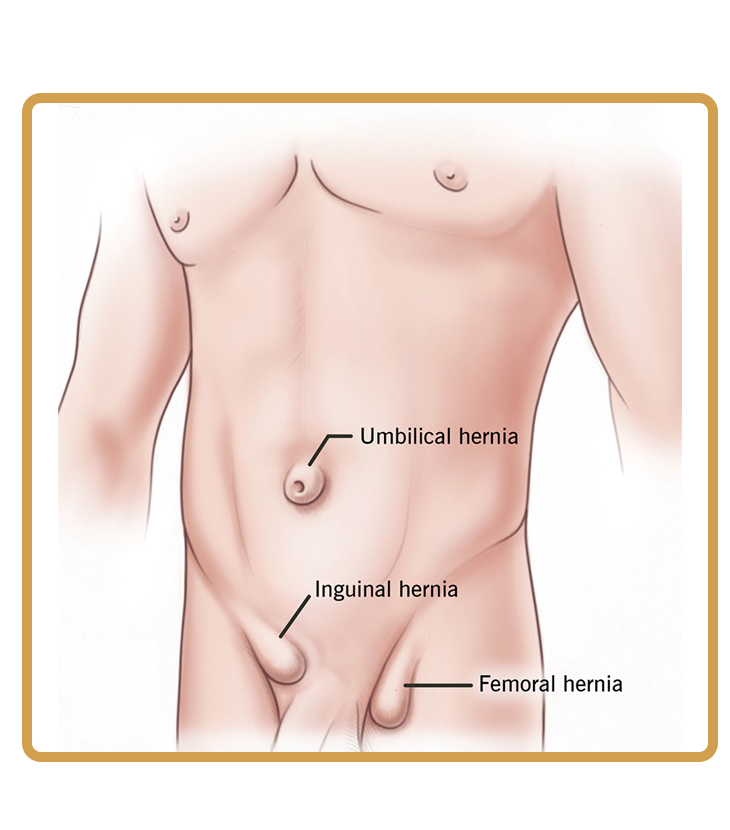

A hernia occurs when an internal organ pushes through a weak spot in the muscle wall, causing a visible bulge and discomfort.

A visible or noticeable bulge in the abdomen or groin often indicates a hernia and should be examined by a surgeon to avoid pain, complications, or enlargement.